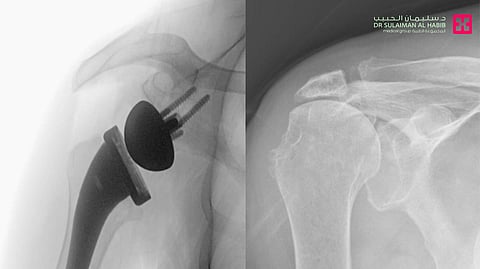

وقال د. علاء محمد حمدان؛ استشاري جراحة العظام والمفاصل، رئيس الفريق الطبي المعالج، إن المراجع زار المستشفى مشتكياً من أعراض متزايدة، بدأت بآلامٍ في الكتف اليمنى، ثم تطوّرت تدريجياً مع مرور الوقت، إلى أن أصبح عاجزاً عن رفع ذراعه، وعن أداء مهامه اليومية، مضيفاً أن الفريق الطبي بعد المعاينة السريرية أجرى له حزمة فحوصات طبية دقيقة؛ مخبرية وأشعة الرنين المغناطيسي Mri، والأشعة السينية X- ray، وأظهرت النتائج وجود قطعٍ مزمنٍ وانكماشٍ في "3" من أوتار الكتف، مع عدم إمكانية ترميمها أو إصلاحها، كذلك ضعف وضمور في العضلات واحتكاك في المفصل.

واستطرد د. حمدان موضحاً، أن الفريق الطبي درس الحالة، وخَلُصَ إلى أن التدخُّل المناسب للحالة هو استبدال مفصل الكتف، وبعد اتخاذ الترتيبات اللازمة، أُجريت له عملية جراحية نوعية، تمَّ فيها أولاً تنظيف محيط المفصل القديم من التكلسات والزوائد العظمية المسبّبة للاحتكاكات، ومن ثم تركيب المفصل الصناعي الجديد الذي يناسب الحالة، ويتميّز بجودته العالية، إذ يساعد على تحقيق المرونة الكاملة للمفصل ومجال أكبر للحركة، واستمرت العملية نحو ساعتين، ومضت وفقاً للخطة العلاجية، وتكللت في النهاية جهود الفريق الطبي بالنجاح التام، ونُقل المراجع بعد الجراحة مباشرة إلى جناح التنويم. وبعد ذلك تمّ البدء بتطبيق برنامج العلاج الطبيعي المكثّف، ومن ثم غادر المستشفى إلى منزله بعد "3" أيام وهو بصحة جيدة، وتوقّع أن تختفي الأعراض التي نغصت حياته التي خفت حدّتها بالفعل، بعد الانتهاء من برنامج العلاج الطبيعي المرسوم له، مضيفاً أنه سيعود لممارسة حياته بصورة طبيعية.